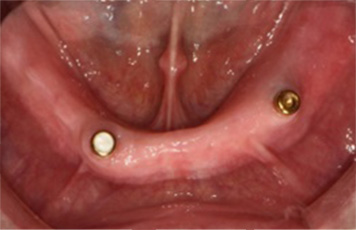

전체틀니 / 부분틀니(임플란트 틀니는 보험 적용 제외)